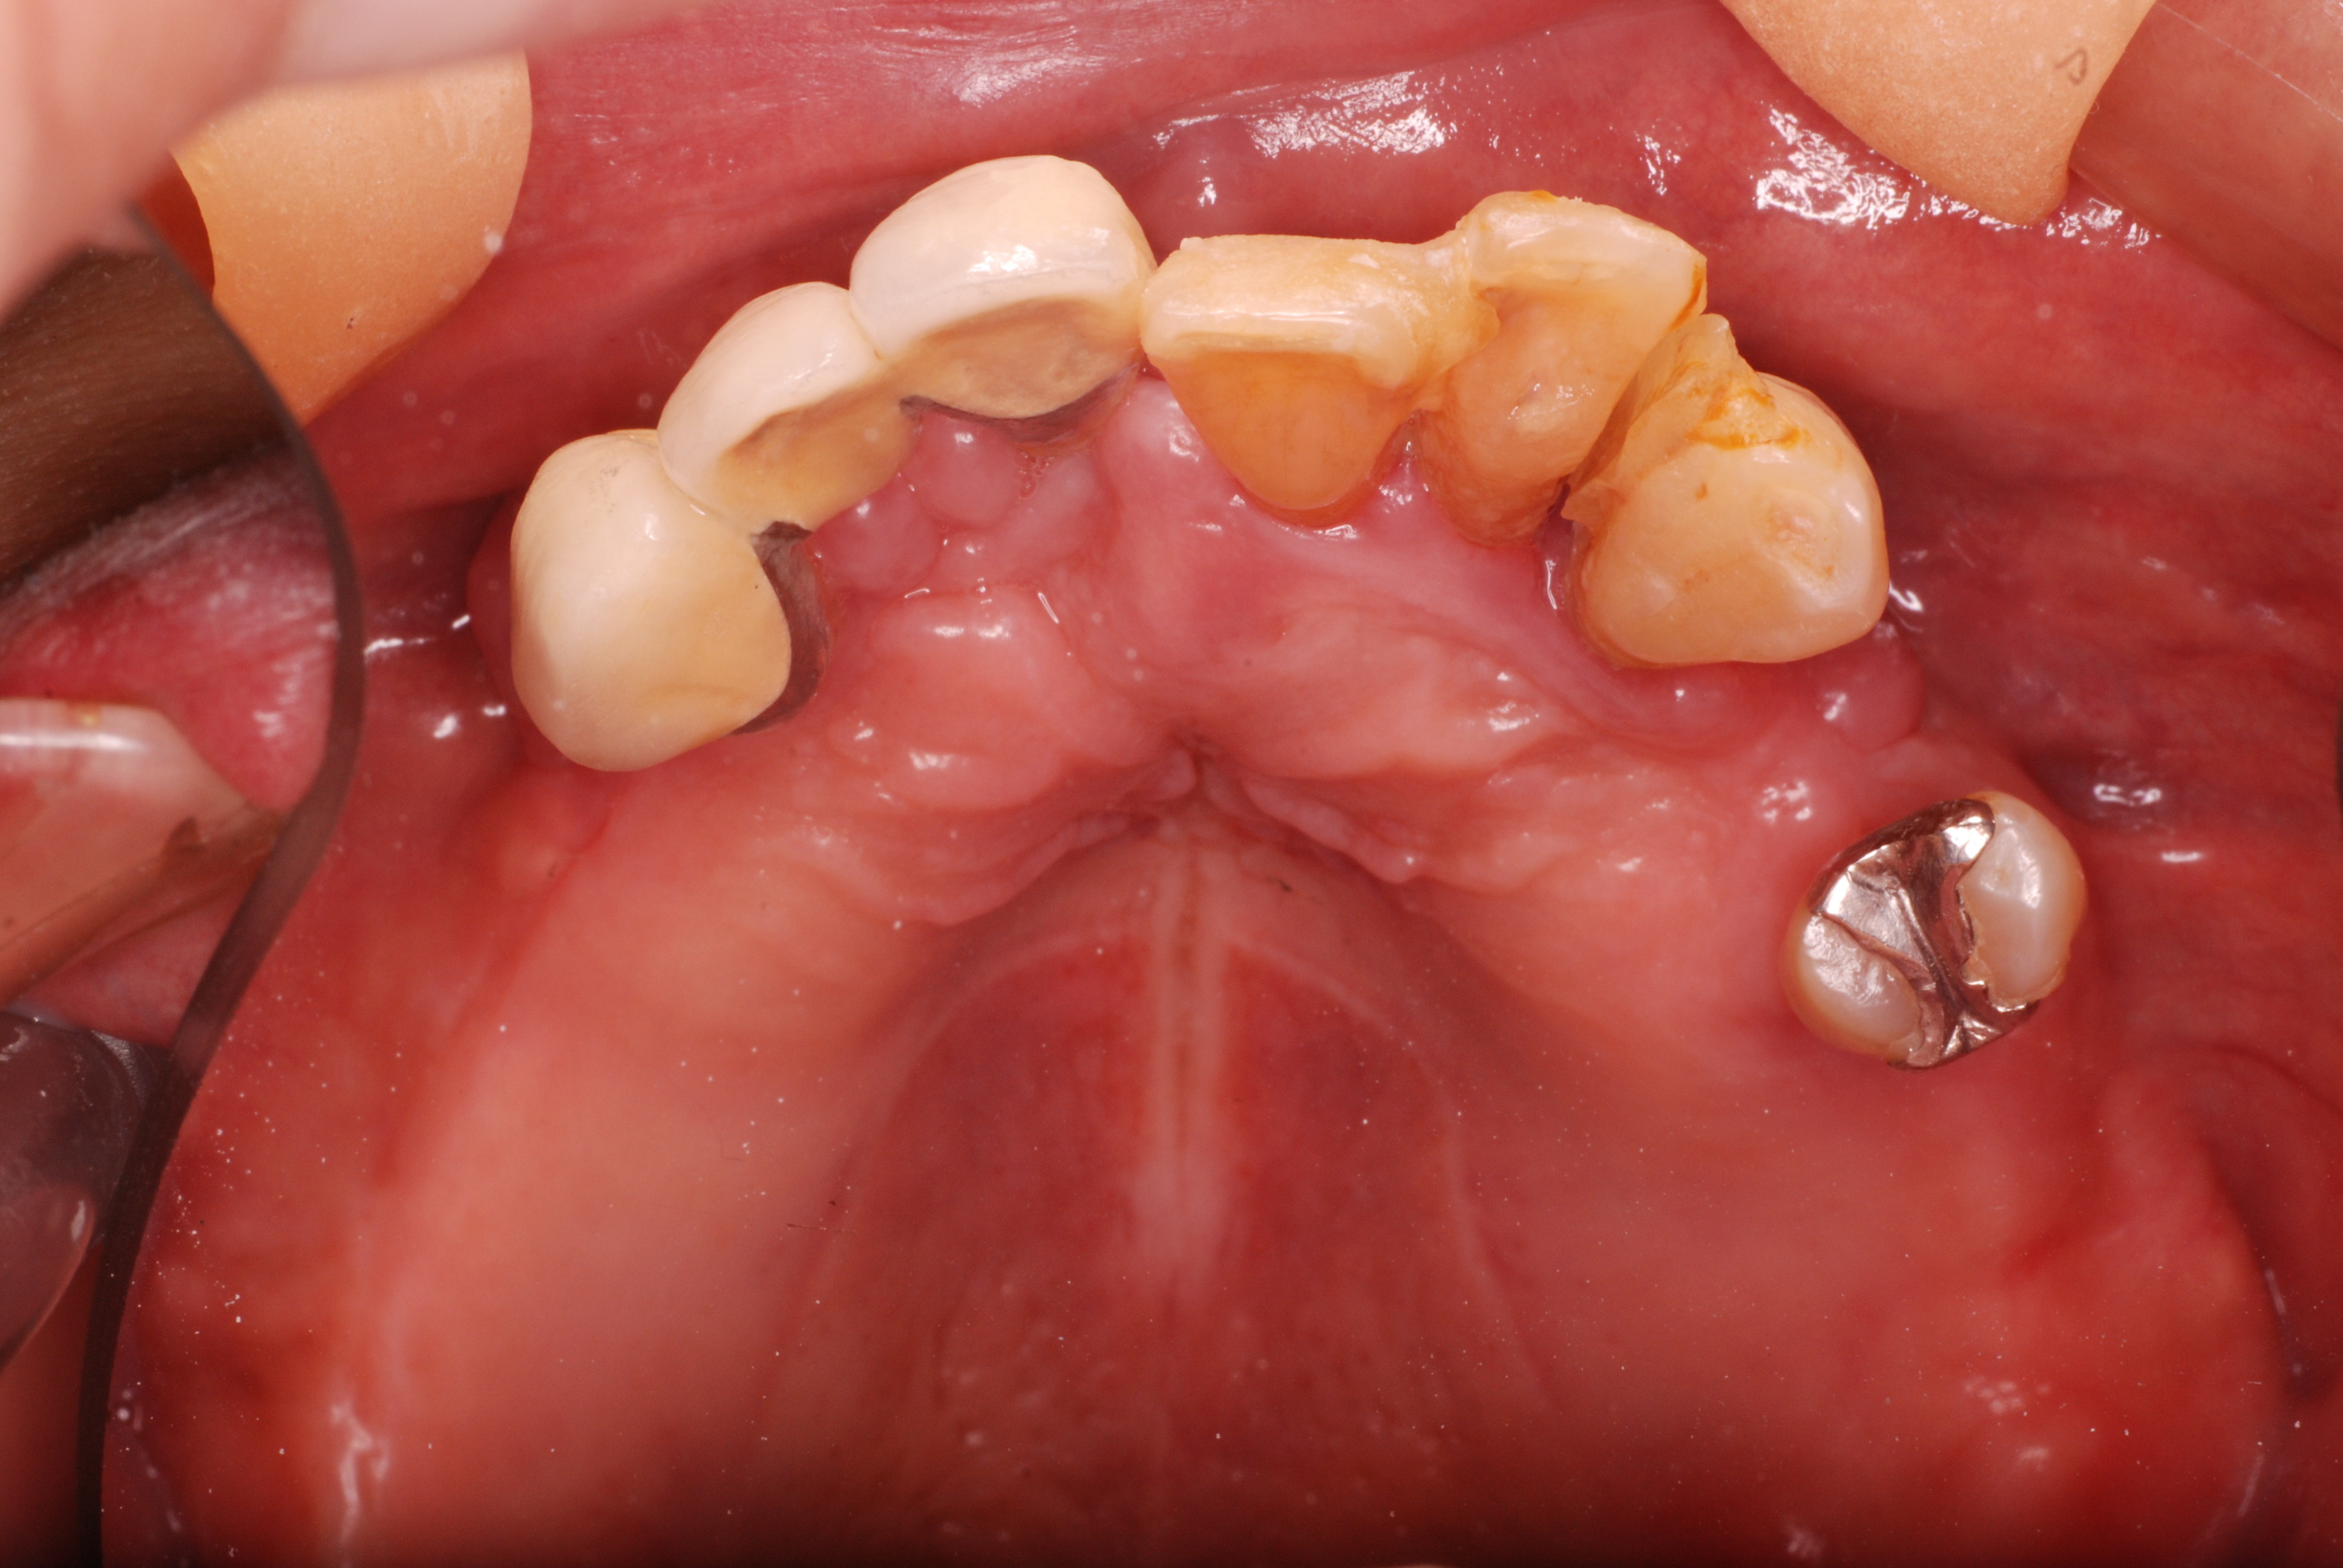

一番奥の銀歯の裏側(舌側)にものすごい虫歯ができていて

穴があいて心配になり受診されました。

セトモノや銀歯を被せたと言っても治った訳ではないのです。

銀歯を外すと歯茎との境目が虫歯という“ばい菌”の塊でボロボロ

でした。

DSC_0005

ばい菌を除去した後の歯です。神経を取り削り被せた歯というのはセトモノであろうと銀歯であろうとこのように殆ど健康な部分はないのです。

磨かなければ、磨けなければ“助からないのです。”